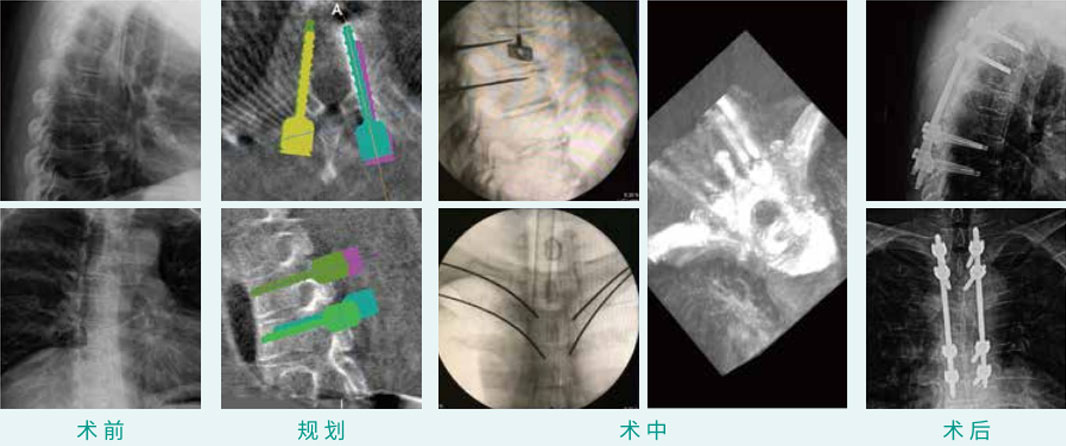

椎弓根钉经皮内牢靠术

天玑? 辅助T2, T3, T6, T7椎弓根钉经皮内牢靠术

基本情形:患者男,,,,,,55岁

机械人累积用时:20分钟

植入物:8枚经皮椎弓根螺钉

病例泉源:中国医科大学隶属第一医院 朱悦 丛琳